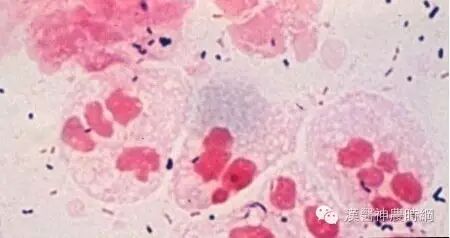

淋球菌为革兰阴性的卵圆形或球形菌,常成双排列,两菌的接触面扁平或微凹,大小为0.6~0.8μm。无鞭毛无荚膜,也不形成芽孢。在脓液标本中淋球菌位于白细胞内。在含有动物蛋白质的培养基上生长繁殖良好,生长环境的最适pH值为7.0~7.5,最适温度为35~36℃,在5%~10%二氧化碳环境中可缩短培养期。20~48h后观察菌落为圆形、凸起、湿润、光滑、半透明、灰白色、边缘呈花瓣状。根据菌落大小、光泽等分T1~T5五种类型,T1和T2两种菌落为毒性菌株,菌体表面有菌毛;T3,T4和T5为无毒菌株,菌体表面无菌毛。

取患者尿道分泌物或宫颈分泌物,作革兰染色,在多形核白细胞内找到革兰阴性双球菌。女性宫颈分泌物中杂菌多,敏感性和特异性较差,阳性率仅为50%~60%,且有假阳性,因此世界卫生组织推荐用培养法检查女性患者。慢性淋病由于分泌物中淋球菌较少,阳性率低,因此要取前列腺按摩液,以提高检出率。咽部涂片发现革兰阴性双球菌不能诊断淋病,因为其他奈瑟球菌属在咽部是正常的菌群。另外对症状不典型的涂片阳性应作进一步检查。